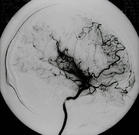

烟雾病又名脑底异常血管网,是一组以颈内动脉虹吸部及大脑前、中动脉起始部狭窄或闭塞,脑底出现异

常的小血管网为特点的脑血管病。因脑血管造影时呈现许多密集成堆的小血管影,似吸烟时吐出的烟雾,故名烟雾病。

脑血管造影可以发现颈内动脉起始部、大脑前、中动脉起始段狭窄或不显影,基底节区可见大量细小血管团如吸烟吐出的烟雾。此外可见脑内形成侧支循环代偿支。随着病程的延长,代偿吻合支的数量逐渐减少或缩小。

5.脑血管造影 见颈内动脉虹吸上段和大脑前、中动脉起始部狭窄,脑底烟雾状异常血管网和广泛的侧支循环形成。应与脑动脉硬化性脑梗死和动静脉畸形鉴别。